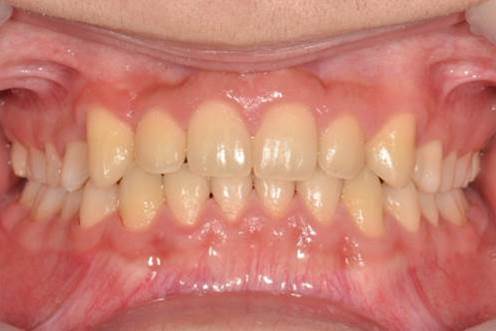

아래턱이 작고 앞니끼리 너무 깊게 물린 케이스입니다. 과개교합교정을 통해 정상교합을 만들었습니다.